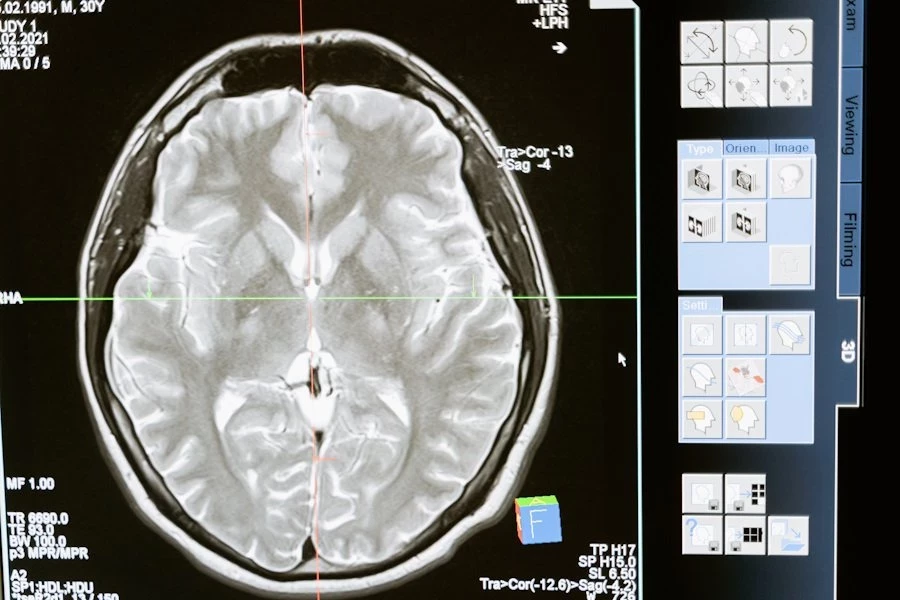

В Harvard Medical School ученые разработали новое лечение для редких опухолей головного мозга, называемых папиллярными краниофарингиомами. Их методика выдала потрясающие результаты в уменьшении размеров опухоли. Они опубликовали свою методику в журнале New England Journal of Medicine.

В исследовании приняли участие 16 пациентов, из которых 15 прошли как минимум один полный цикл терапии с использованием комбинации препаратов в течение 28 дней. После четырех таких циклов средний размер опухоли сократился на 68% до 99%, в среднем на 91%.

Семерым пациентам не понадобилось дополнительное лечение после окончания экспериментов. У шести опухоль не росла и не прогрессировала в течение около двух лет наблюдения. Ни у одного из пациентов опухоль не увеличилась во время лечения, и никто из них не умер.

Ученые отметили, что все пациенты, прошедшие хотя бы один цикл терапии, положительно отреагировали на лечение, и это считается самым успешным результатом среди всех лекарственных методов лечения опухолей головного мозга на данный момент.